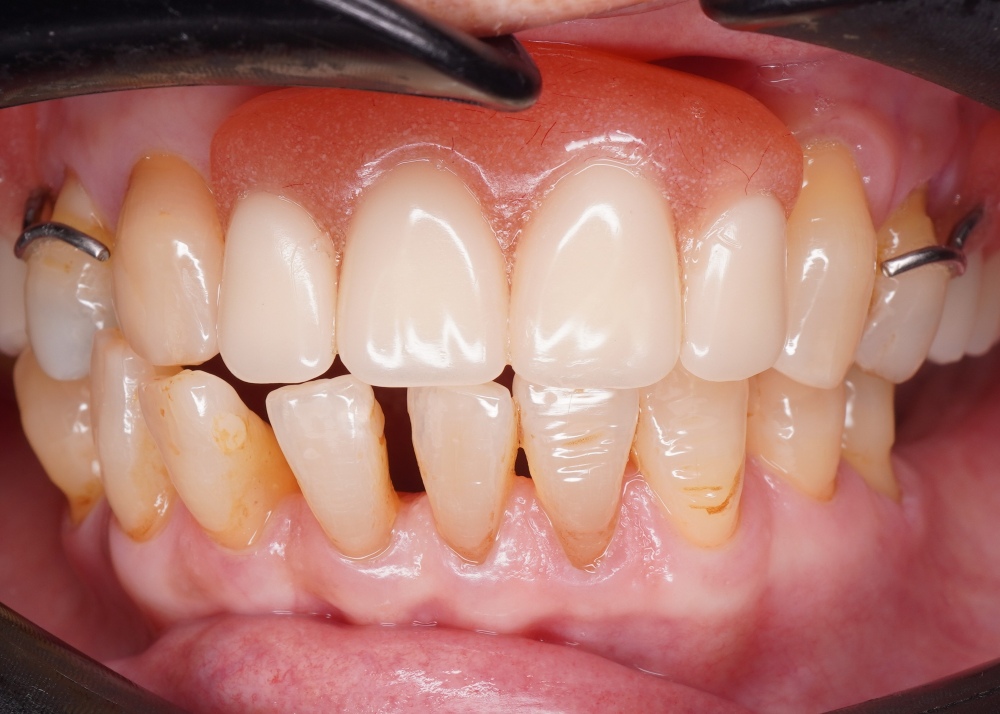

We use a digital intraoral scan to capture a detailed 3D image of your teeth and gums in real time. This helps us detect hidden issues such as cracks, gum problems, or early decay that may be causing your toothache.

We gently loosen the tooth before removal to minimise trauma to the surrounding tissues. This approach makes the procedure more comfortable, faster, and helps reduce swelling after treatment.

Note: